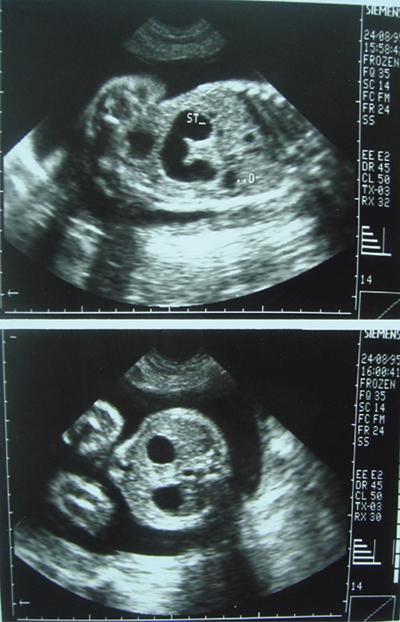

Fig. 7.4.1.1Midline epigastric scan showing symmetrically thickened hypoechoic muscle of the pylorus with central echogenic mucosa.

Ultrasonography (USG) of abdomen: Usually performed in the right lateral decubitus position to allow fluid to distend the antral region.

USG reveals a target sign seen as a thickened hypoechoic muscle mass of the hypertrophied pylorus surrounding the central echogenic thin mucosal line.

USG: This is the preferred imaging modality as it is noninvasive and does not pose any radiation hazard. USG is performed with a 6–10 MHz linear probe. Fluid distention of the stomach can aid in visualization of the pylorus. A sausage-shaped mass with a total thickness of more than 14 mm and length in excess of 16 mm with each wall measuring at least 4 mm is indicative of congenital hypertrophic pyloric stenosis.

USG: Antenatal sonology detect distended stomach and duodenum in a patient presenting with polyhydromnios as seen in the adjacent image

Fig. 7.4.1.3 Antenatal USG reveals double bubble sign with stomach and duodenum distended with fluid.